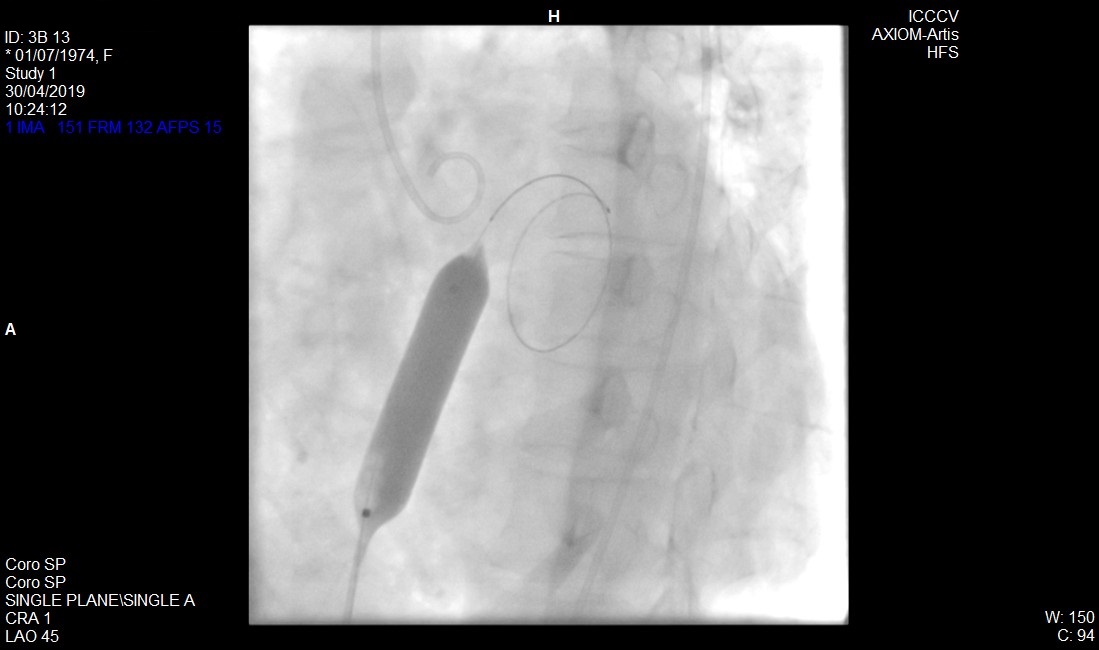

La Septostomía Auricular, representa una alternativa terapéutica más, siendo utilizada como paliativo o escalón previo a la ejecución del trasplante. En nuestro sistema, constituiría el último paso para enfrentar esta enfermedad.

Se expone la introducción, por primera vez, de esta técnica en el país en una paciente con Hipertensión Arterial Pulmonar, la cual presentaba predictores elevados de fracaso y mortalidad transprocedimiento. Fue realizado con éxito y sin complicaciones.

La Septostomía Auricular, constituye una opción de tratamiento que mejora la calidad de vida de estos enfermos.